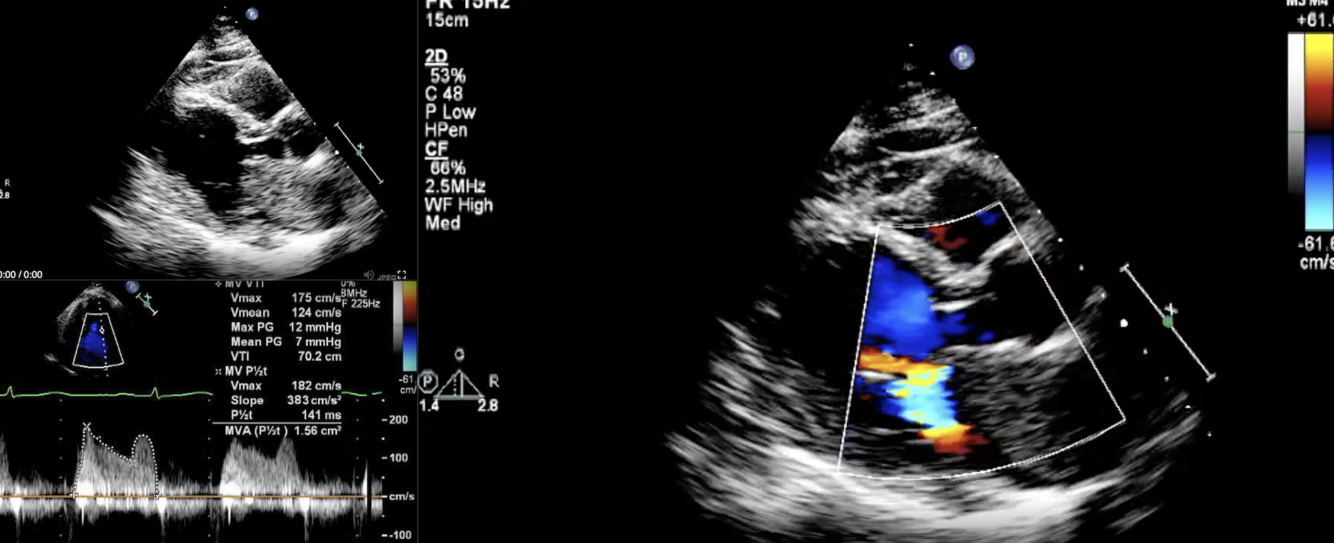

Describe the findings